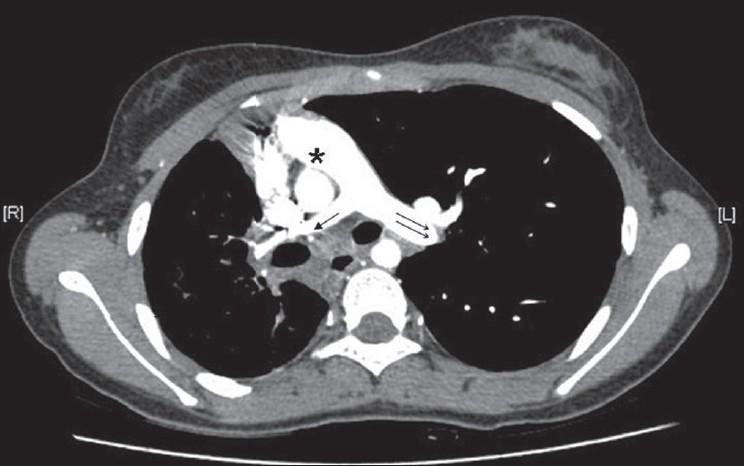

Scimitar syndrome is a rare congenital disorder. It has a varied presentation. In adult life, it usually presents either as recurrent chest infection and/or exertional dyspnea. Pulmonary artery hypertension and hemoptysis both are uncommon features of this syndrome in adult life.

弯刀综合征是一种罕见的先天性疾病。其表现多样。在成年期,它通常表现为反复的胸部感染和/或劳力性呼吸困难。肺动脉高压和咯血在成年期都是该综合征不常见的特征。